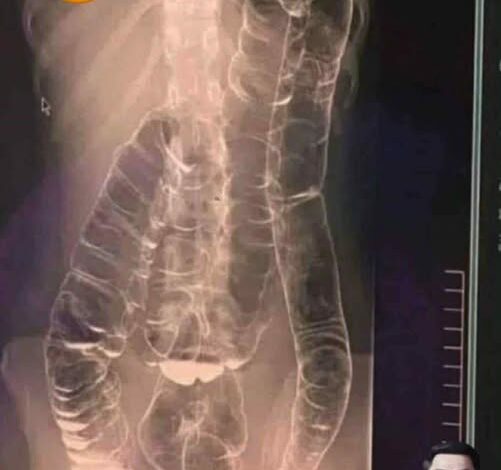

The primary role of the large intestine, or colon, is to absorb water from the residual food matter passing through it and to form solid waste. Constipation occurs when the muscle contractions of the colon are too slow or sluggish, causing the waste to move through the digestive tract at a glacial pace. The longer the waste sits in the colon, the more water is absorbed, resulting in stool that is hard, dry, and difficult to pass. Over time, this chronic backup creates a toxic environment. The body begins to reabsorb metabolic byproducts that were meant to be expelled, leading to symptoms that extend far beyond the gut: brain fog, skin breakouts, persistent fatigue, and a general sense of physical heaviness.

Severe abdominal bloating that causes visible distension, persistent vomiting, or the presence of blood in the stool are indicators of a potential bowel obstruction or an underlying inflammatory condition. In these cases, the “silent killer” may be a symptom of a more aggressive pathology that requires professional diagnostic tools like a colonoscopy or imaging. Ignoring these signs in hopes that the problem will resolve itself can lead to life-threatening complications such as a perforated bowel or systemic sepsis.